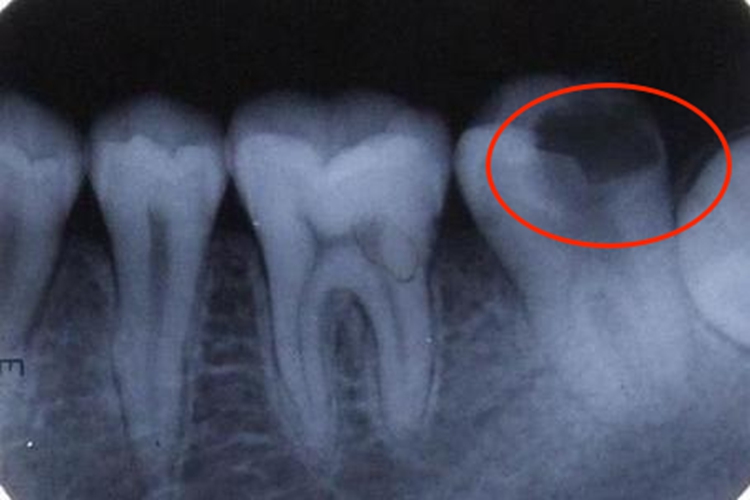

常见牙齿异常为龋齿。对于隐蔽的龋损,在不能直接视诊,且探诊也有困难时,可通过X线片检查辅助诊断,如邻面龋、潜行龋和充填物底壁及周缘的继发龋。龋损区因脱矿而在牙体硬组织显示出透射度增大的阴影,确定诊断。